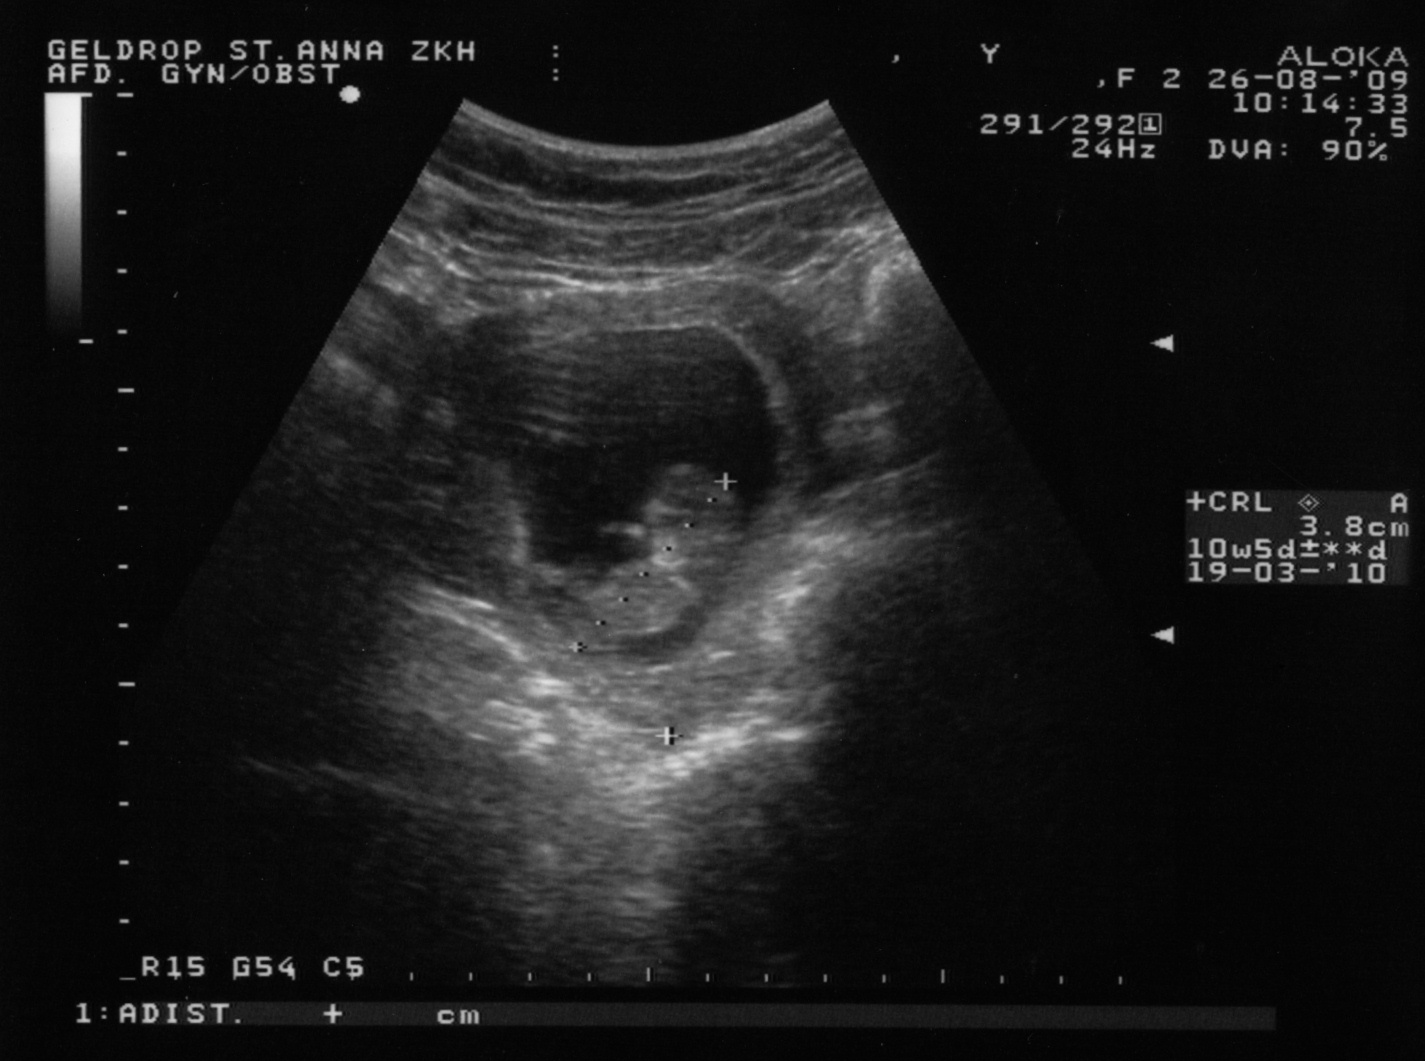

Hallo allemaal! Hieronder de eerste foto (klikken voor een grotere) en eerste video van ons Kleintje!